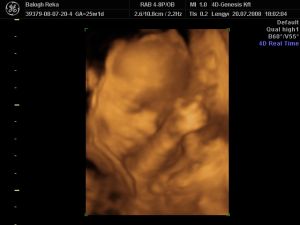

Na, most jöttem meg a 4d-ről.Annyira jó volt, nem hittem a szememnek.Láttam a kis nuniját, a szeméremajkait.

Már majdnem 1,5 kiló, mindene megvan, a kis fülei hihetetlenek voltak.És képzeljétek, mintha tudta volna, hogy produkálnia kell magát, mert ráncolta a homlokát, ásitott, ivott, mosolygott, és integetett. Mindene ok, tele volt épp a gyomra is meg a hólyagja is.Ja, és tök husi a pofija, olyan hörcsög...Nagyon nagyon édes.És mintha tudta volna, hogy lassan vége a vizsgálatnak, befordult a lepény mögé aludni.Ja, és tök hosszú a haja. Kis édes.

Szóval, ezt a 4d Genesist csak ajánlani tudom, nagyon profik, 30 perc az nem 25 és nagyon kedves a nő.